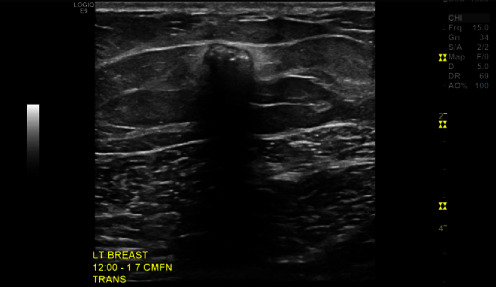

Background: Unintentionally retained foreign bodies in the breast are a rare phenomenon. Most reported cases are iatrogenically derived from surgeries and procedures. Only a handful of reported cases refer to noniatrogenic causes, including bullets, a sewing needle, and a headscarf pin. However, there are no reports to date that describe a retained foreign body in the breast after a motor vehicle collision or a similar traumatic event or from a decorative steering wheel emblem decal. Case Description: We report the case of a 25-year-old female who was involved in a motor vehicle collision with airbag deployment that led to a left breast retained foreign body, a steering wheel emblem decal. On presentation to the emergency room, she reported left chest pain associated with a puncture wound lateral to the left nipple. Imaging at that time was consistent with a metallic object embedded in the subcutaneous tissue of the left breast. Four months after the accident, the patient continued having daily burning pain in the associated area. As such, surgical excision was recommended, and wire-localized excision of the foreign body was subsequently performed. Grossly, the foreign body appeared as a metallic object with rhinestones, which the patient confirmed was a decorative emblem decal that was on her steering wheel. The postoperative course was uncomplicated, and follow-up examinations revealed resolution of the left breast pain. Conclusions: This case underscores a unique presentation after a common accident-a retained foreign body in the breast after a motor vehicle collision-and its successful surgical intervention leading to a favorable postoperative course. Notably, the National Highway Traffic Safety Administration recently advised drivers against adding decorative emblem decals to their steering wheels for this reason. The case therefore highlights safety precautions that should be taken regarding the addition of this type of accessory.

Abstract Image